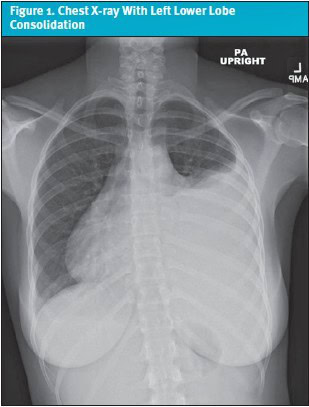

Despite this, her symptoms persisted and gradually worsened. Over the following 2 weeks, she developed intermittent fevers with a peak temperature of 102.6°F (39.2°C), pleuritic chest pain radiating to the back, shortness of breath, and left breast discomfort. She was re-evaluated for a presumed viral upper respiratory tract infection; however, viral panels were negative, and no infectious etiology was found. Given the persistence and evolution of her symptoms, a chest x-ray was obtained. Imaging revealed left lower lobe consolidation suggestive of pneumonia, along with a moderate left pleural effusion and a small right pleural effusion (Figure 1). She was started on a course of amoxicillin and inhaled albuterol.

Clinical Presentation: A 16-year-old, previously healthy girl presented urgently to her pediatrician with a 4-week history of persistent left-sided chest pain. She was initially treated for presumed gastroesophageal reflux disease with omeprazole after presenting on December 5, 2023. Over the following 4 weeks she developed intermittent fevers, shortness of breath, and pleuritic chest pain. A chest x-ray on December 29, 2023, revealed bilateral pleural effusions and left lower lobe consolidation. Despite antibiotics, symptoms worsened, leading to admission on January 2, 2024.